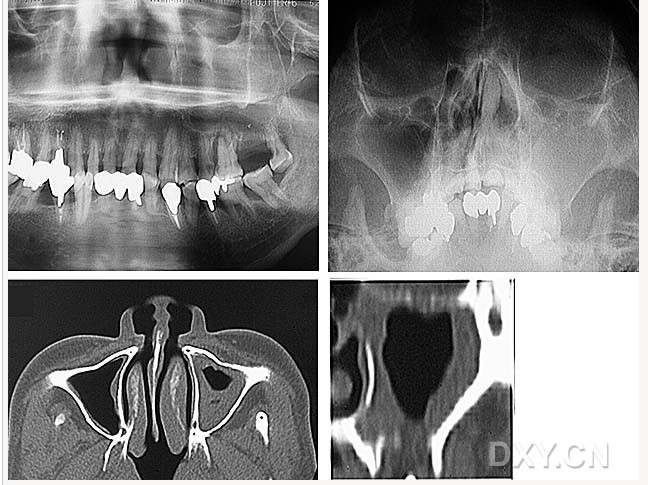

鼻鄂囊腫

鼻腭囊腫

鼻竇炎(注意不要誤診呀)